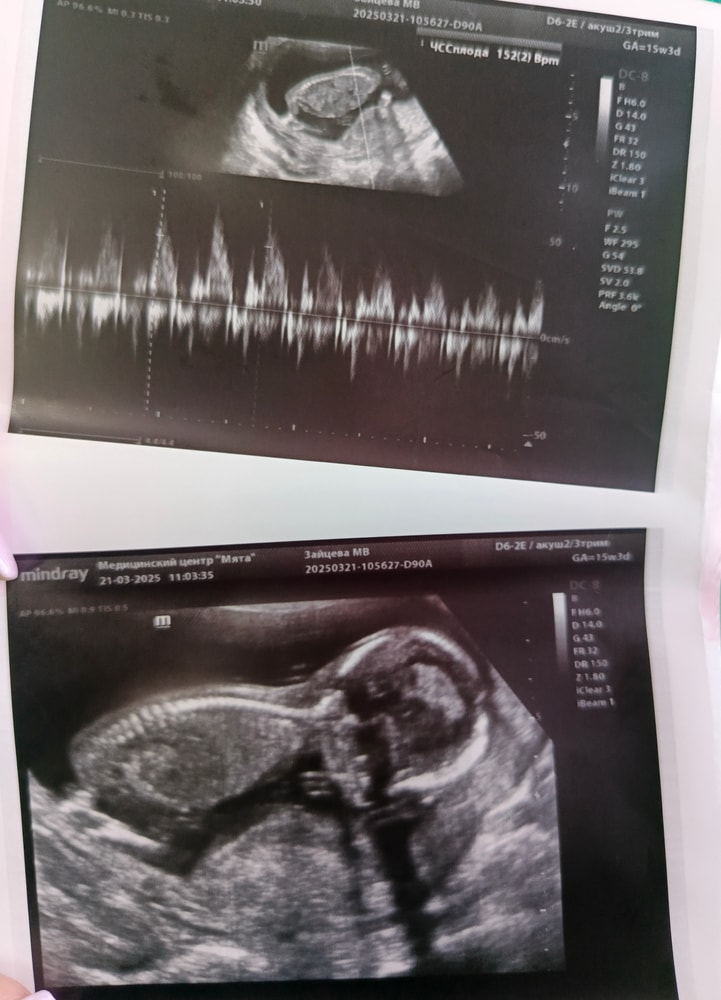

Сходили на узи, посмотрели пол💓

На этих фотках нет пола)) Но раз врач сказала, точно девочка))))

Поздравляю, а фото с пЫской не будет? Чисто по позвоночнику конечно девочка🫣

Ирина, распечатала мне только такие🤷 но уверенно сказала, что девочка , пуповины между ног не было, четко всё видно по её словам)

Елена, 15,4 сегодня)